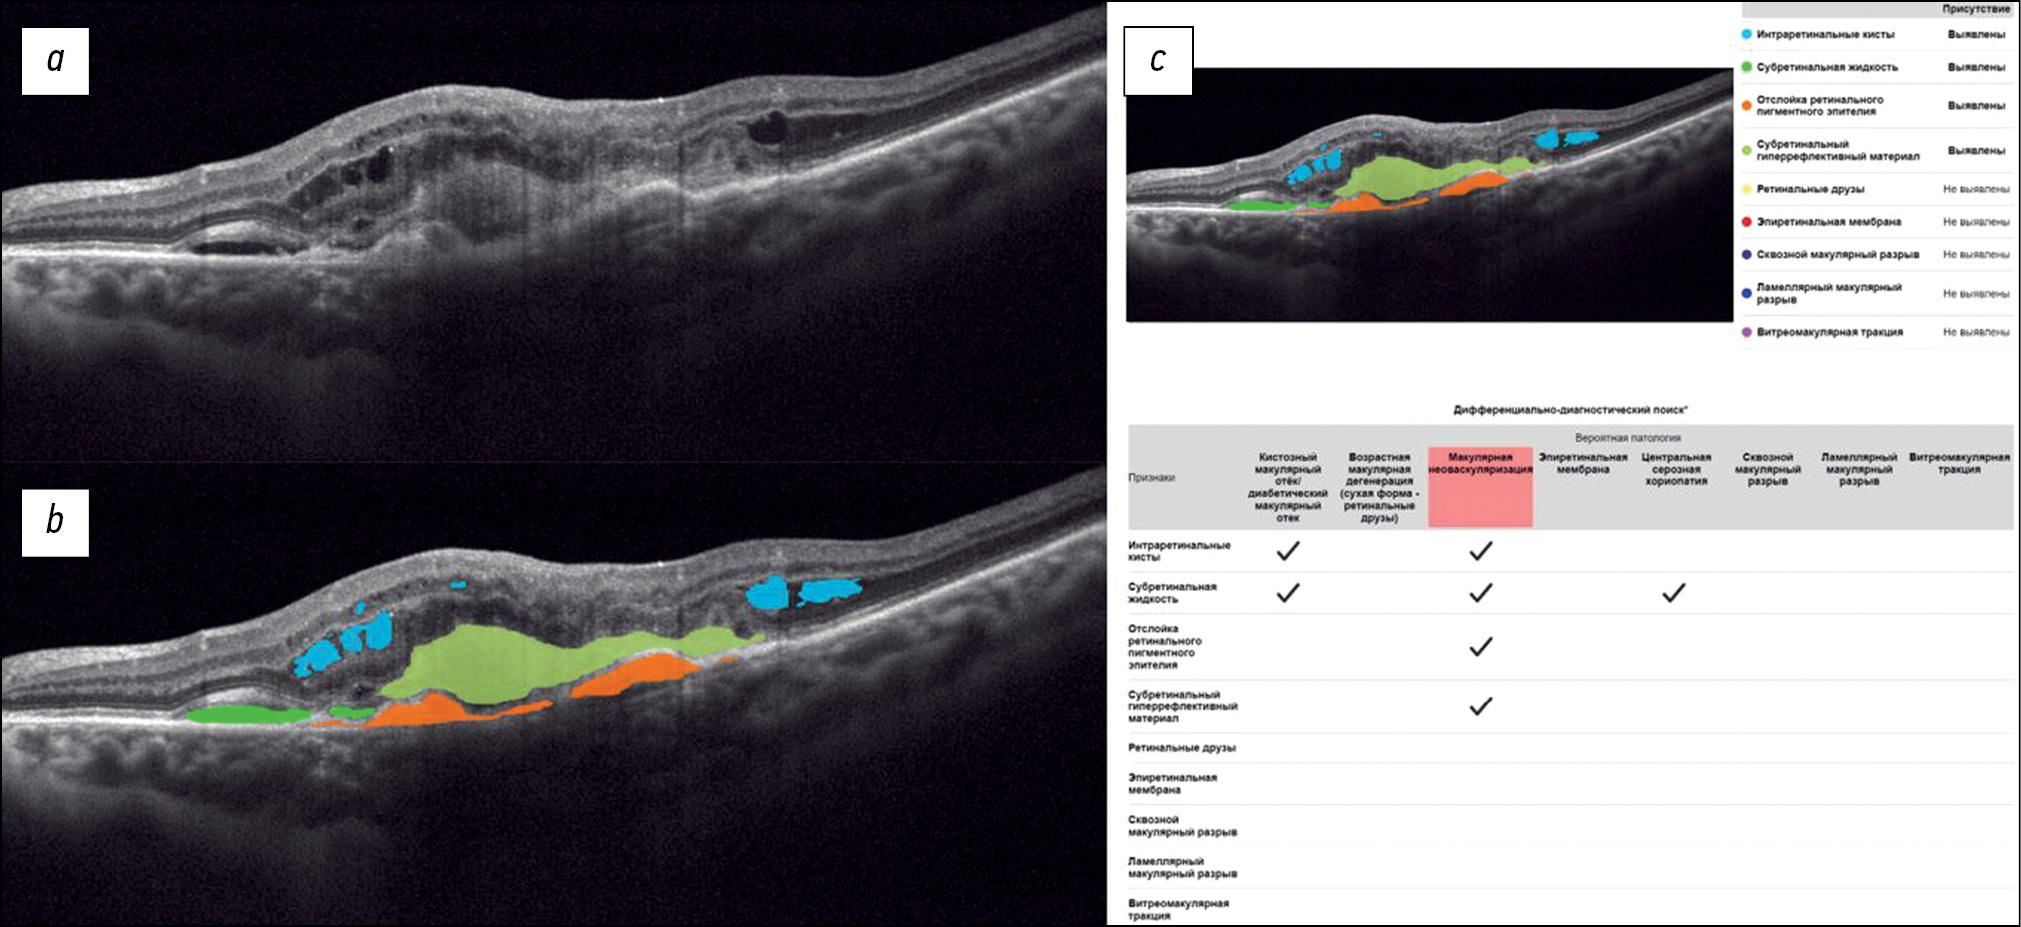

Fig. 2 shows a structural OCT scan of the macular zone of patient B (68 years old) with exudative AMD. The diagnosis was established by an ophthalmologist. In the analysis of the structural OCT scan by Retina.AI, the algorithm segmented the following pathological signs: intraretinal cysts, subretinal fluid, retinal pigment epithelium detachment, and subretinal hyper-reflective material. The program report registered macular neovascularization.

Fig. 2. An example of the optical coherence tomography scan analysis of a patient with exudative age-related macular degeneration by the artificial intelligence algorithm: a — structural optical coherence tomography scan; b — optical coherence tomography scan after segmentation of the pathological features (subretinal fluid — green mask, intraretinal cysts — blue masks, retinal pigment epithelium detachment — orange mask, subretinal hyperreflective material — yellow mask); c — scan analysis report (the reporting table of the differential diagnostic search, probable pathology is highlighted in red — macular neovascularization).